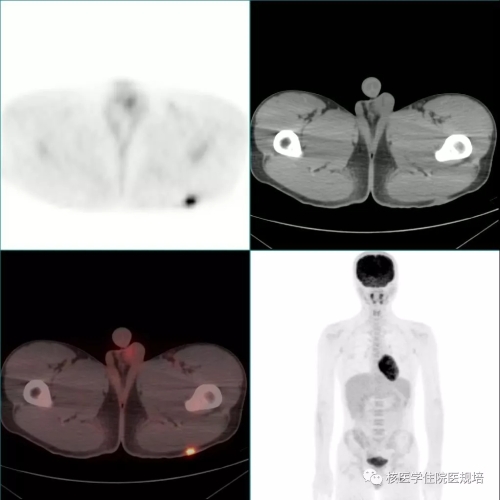

患者男性,20岁,2月前因发热待查就诊,影像学检查发现心脏占位。心脏超声示:左室前侧壁占位,彩色多普勒血流成像可见肿物血供丰富(图1);心脏MR示:左室中段及心尖段前侧壁占位,累及前组乳头肌,前侧壁可见粗大肿瘤血管(图2)。为明确左心室病变性质,行18F-FDG PET/CT显像(图3)。

图1